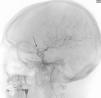

Más datosMujer de 49 años que sufrió una primoconvulsión. Se realizó una TC de cráneo (fig. 1) que objetivó un aneurisma gigante en la arteria carótida interna (ACI) izquierda, trombosado de forma subtotal (no captaba contraste en el angio-TC). Se decidió realizar una arteriografía (fig. 2) que describía un gran aneurisma carótido-oftálmico izquierdo, con una mínima porción permeable (8×5mm), el resto lo describen trombosado. Durante la arteriografía hizo focalidad con hemiparesia y desviación de comisura vocal, con vasoespasmo arteriográfico, que cedió tras administrar verapamilo. Se realizó una RM (fig. 3) que describía el aneurisma con localización paraselar frontal izquierda de 4,2×3,9×3,6cm con origen en el top de la ACI izquierda, presentando efecto masa sobre ambas arterias cerebrales anteriores, arteria cerebral media izquierda, así como compresión y desplazamiento derecho de ambas astas frontales. En el estudio de angio-RM se delimitó una dilatación sacular de 9mm en la porción supraclinoidea de la ACI izquierda, localizada en el tercio inferior del seno de la lesión descrita. Sugieren diagnóstico diferencial con rotura contenida del aneurisma. Se decidió intervención quirúrgica de clipado del aneurisma, que confirmó trombosis parcial del mismo con cápsula íntegra. Tras esto, la paciente se encuentra sin focalidad y como única complicación posterior ha desarrollado un síndrome pierde-sal.